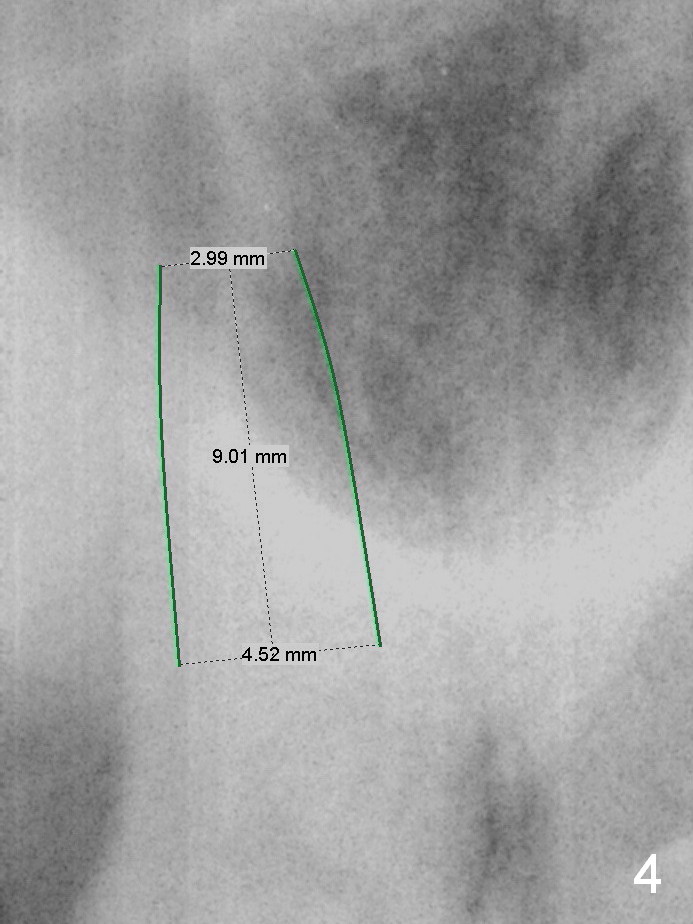

A 54-year-old woman has nocturnal pain at the tooth #2 (Fig.2), one year after extraction of the tooth #14 (Fig.1). A mesiodistal crack line is found at root canal therapy (Fig.3 arrowheads). The tooth appears to be nonsalvageable. The socket is either single or 3. Cut and soak 3 large pieces of gauze in Metronidazole. When the tooth is extracted, we will decide whether the gauze needs to be cut further. Depending upon the size of the septum, a relatively small (4.5x9 mm Fig.4) or large (6.5 mm) implant will be placed. The largest pair abutment will be installed to close the socket.